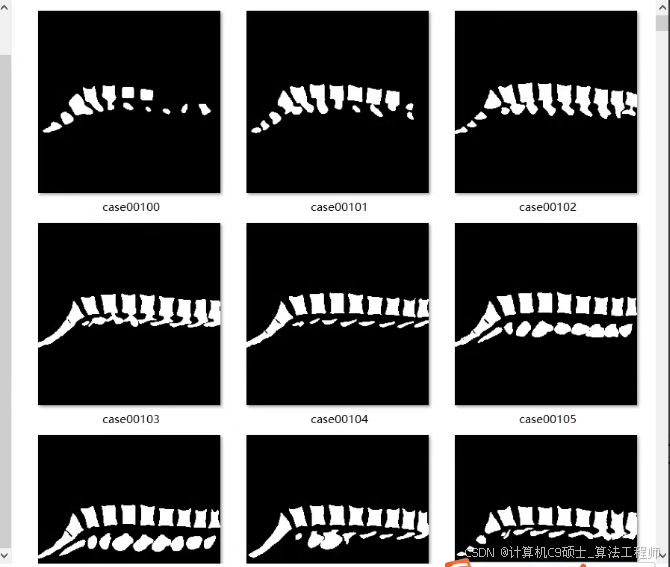

包含脊椎分割数据集:

原图,标签分别2460张

原图,标签分别2460张在这里插入图片描述